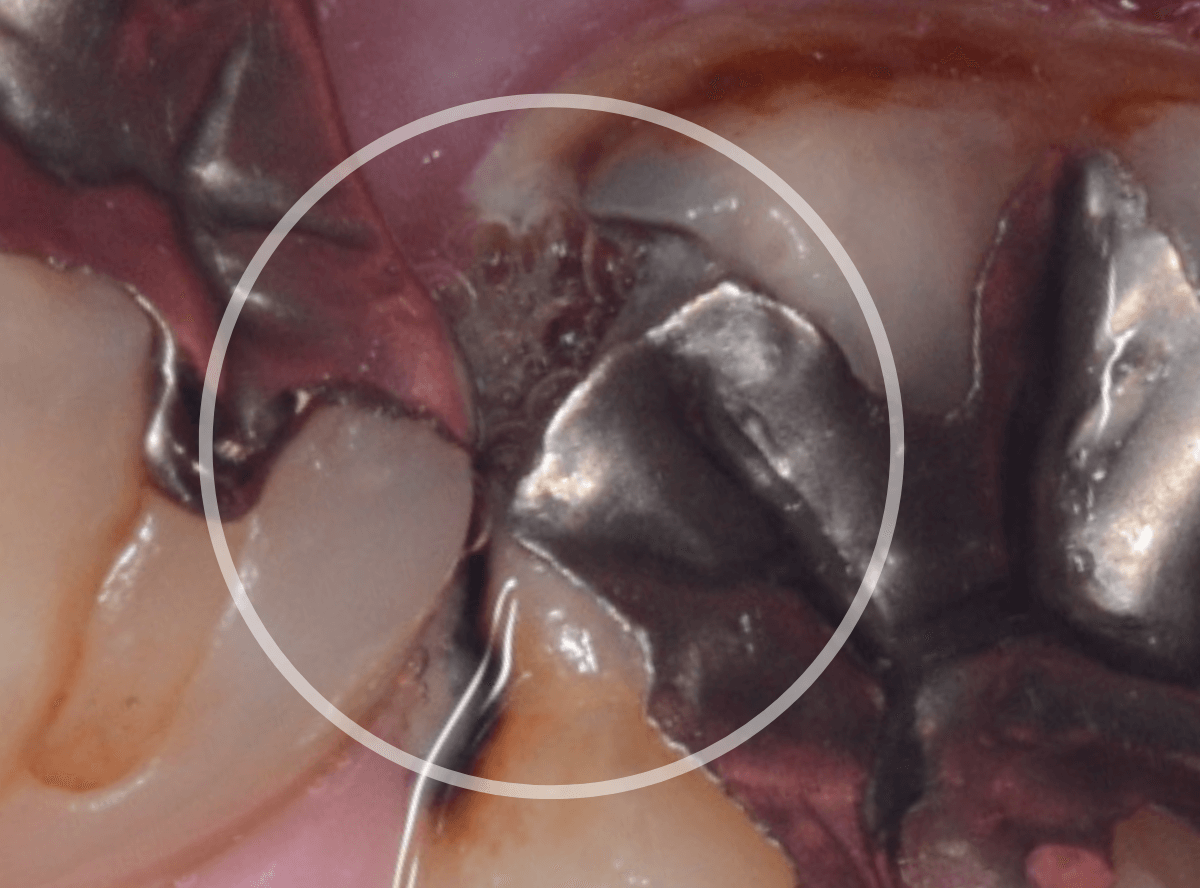

〇部分は前の治療時にしいたセメントです。この下に虫歯が広がっていると思われます。

セメントを除去したところです。

赤く染め出されているところが虫歯です。

神経に近くなっていますので、診療に虫歯を除去します。

側面のレジンや隣の歯との間の虫歯も慎重に除去します。

かなり広く虫歯が広がっています。